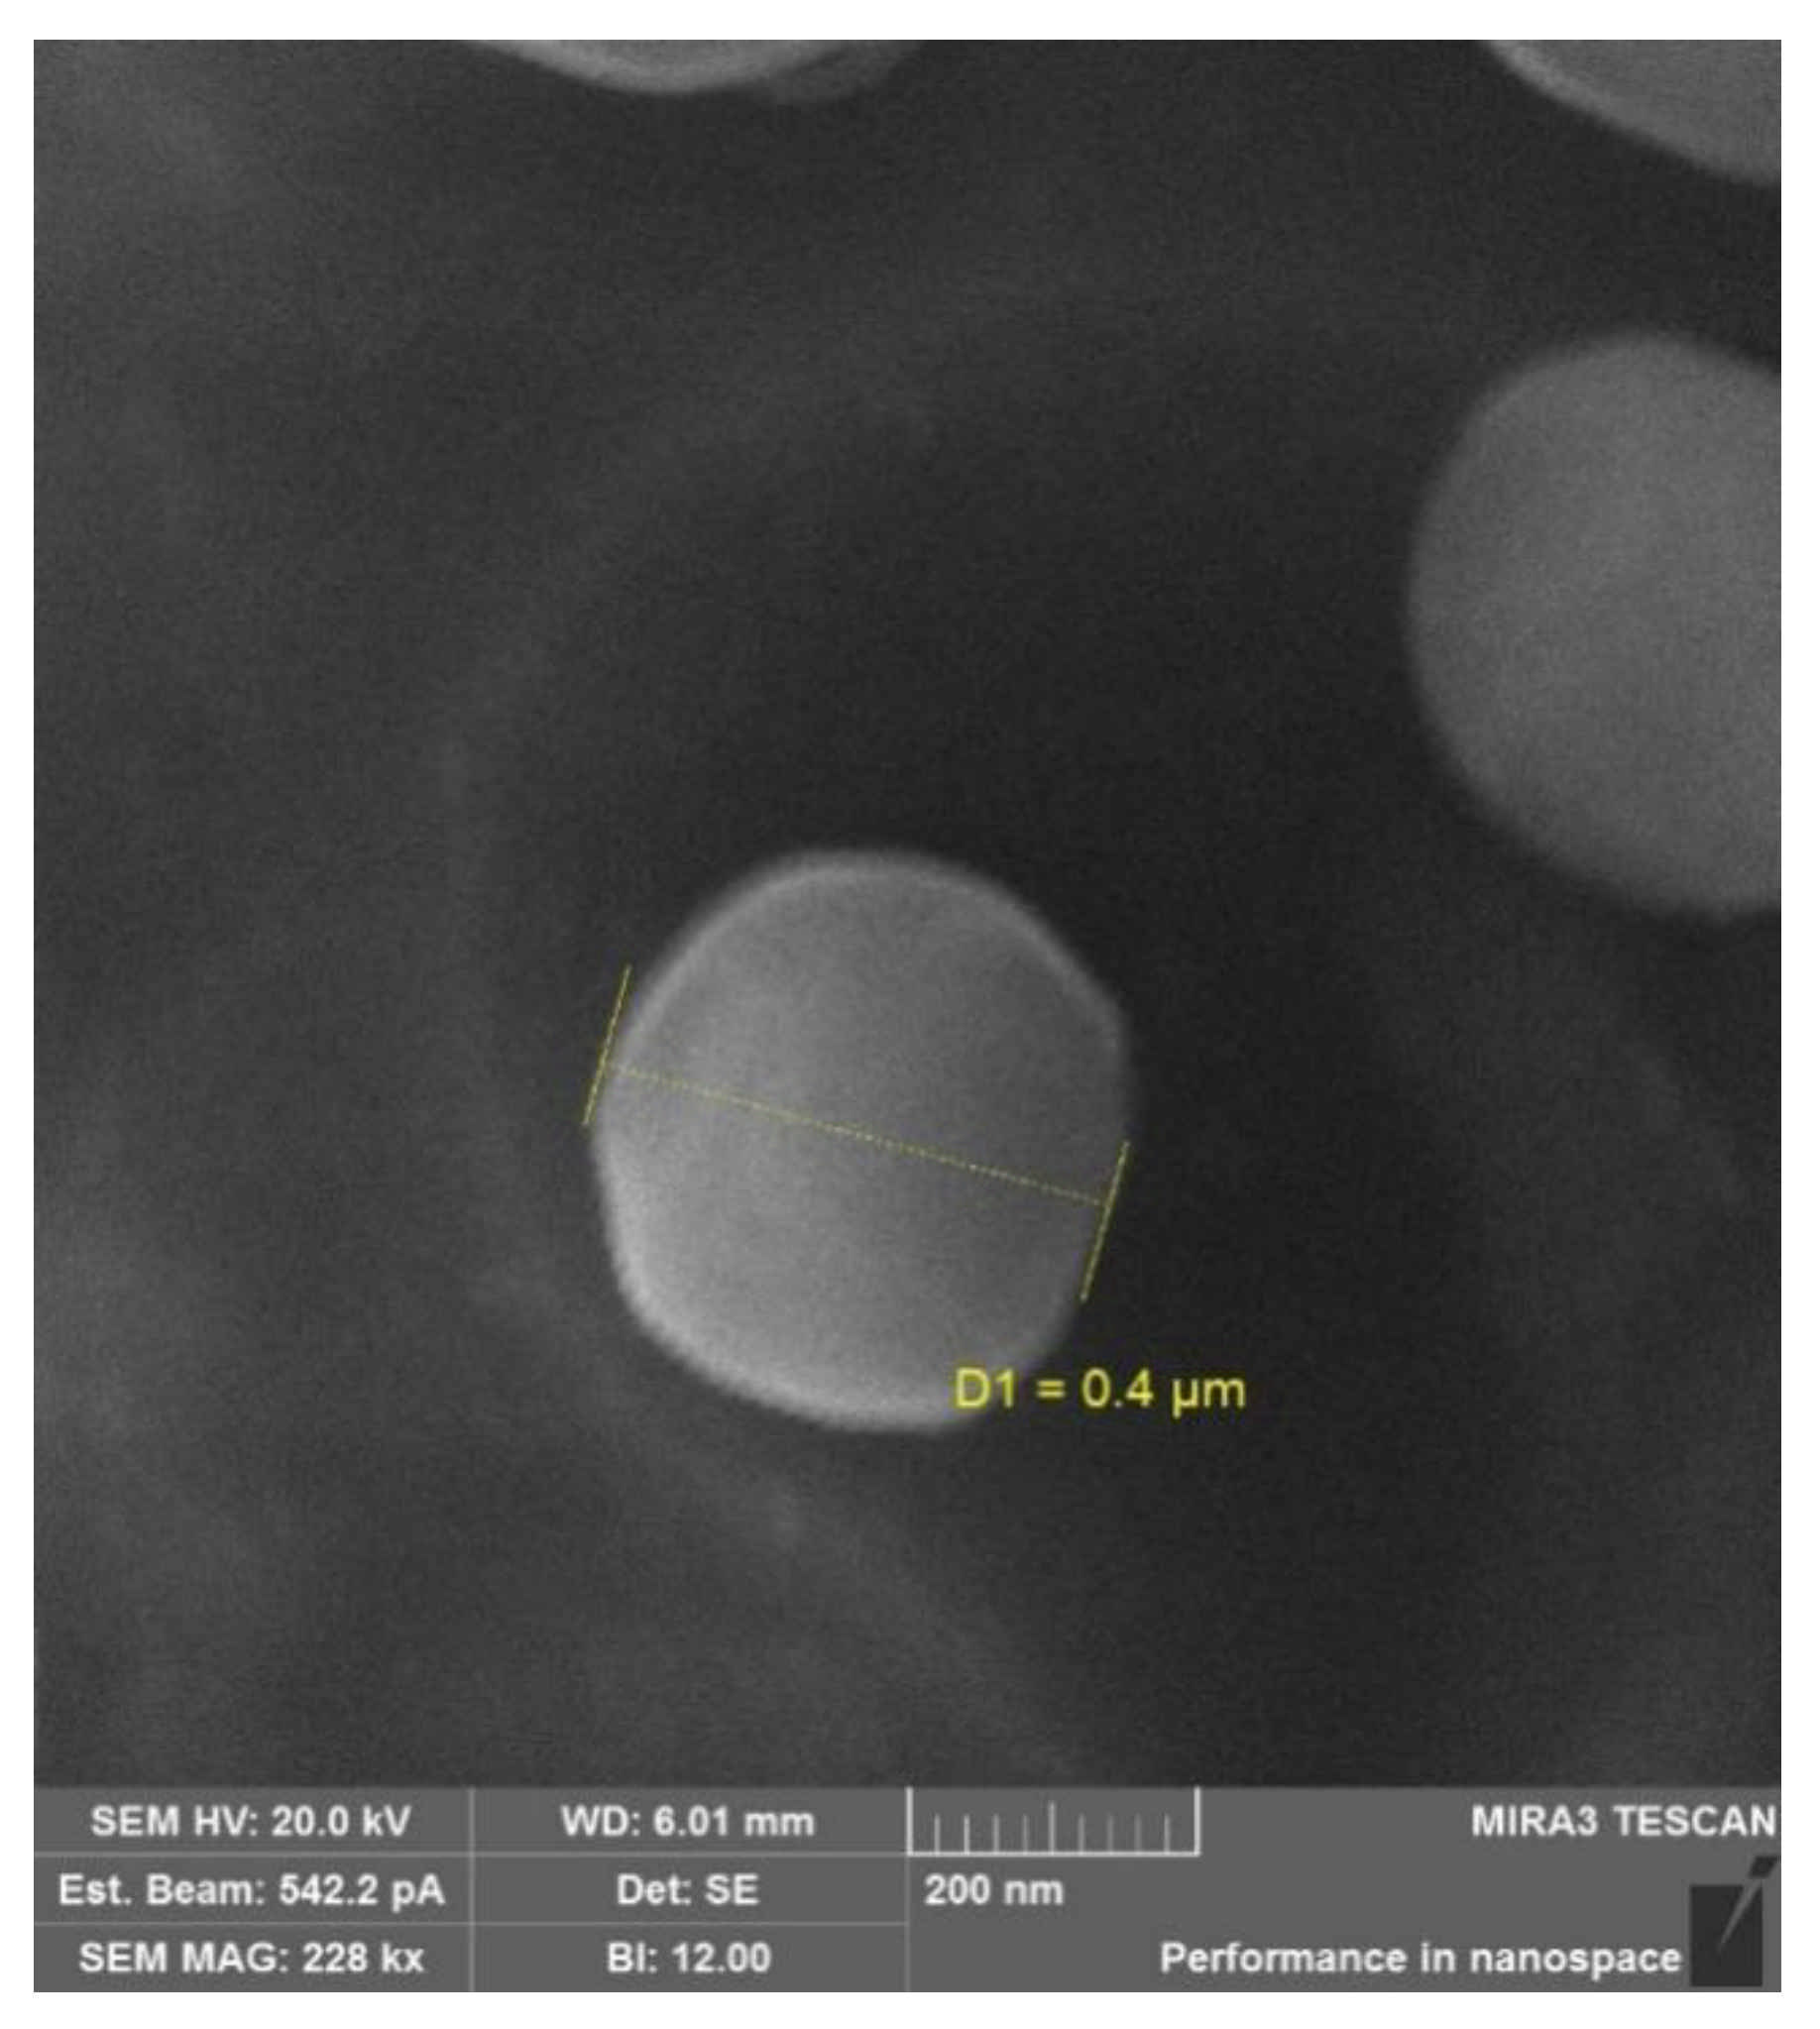

| Sample | 2Rh (nm) | ζ-Potential (mV) |

|---|---|---|

| CS-DEX-5 | 816 ± 268 | 22.5 ± 0.5 |

| SucCS-DEX-5 | 916 ± 326 | −32.1 ± 0.5 |

| CS-DEX-10 | 700 ± 252 | 14.9 ± 0.8 |

| SucCS-DEX-10 | 950 ± 330 | −30.9 ± 0.7 |